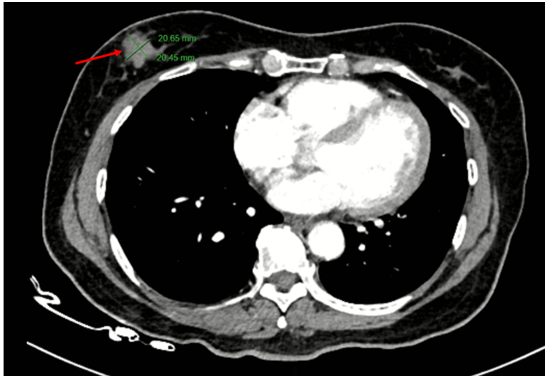

Chụp cắt lớp vi tính lồng ngực: Không phát hiện hình ảnh bất thường ở nhu mô vú phải.

Hình 6.

Hình ảnh CT u vú trước điều trị (bên trái) và sau điều trị (bên phải): Trước điều trị: 1/4 dưới ngoài vú phải có nốt đường kính 20mm, bờ ranh giới không rõ, ngấm thuốc sau tiêm. Sau điều trị: Không phát hiện hình ảnh bất thường ở nhu mô vú phải.